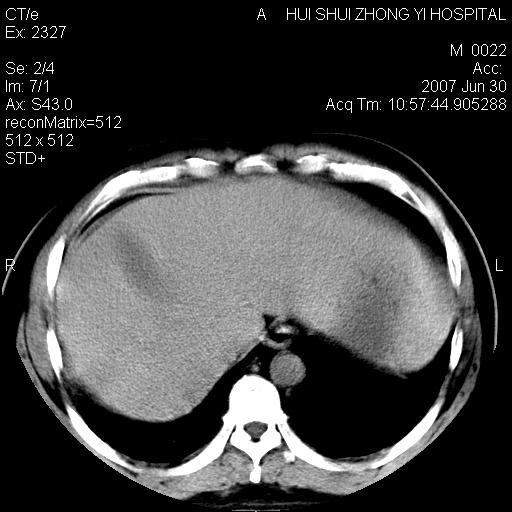

肝右叶密度减低区?

支持双肾结石,肝右叶低密度影为胆囊部分容积效应。

肝右叶低密度影为胆囊部分容积效应?为什么s43.0层面下来不见胆囊影,而是相隔了一层才见胆囊影。这是按我们扫描的顺序发的,但是是追加扫描的。

肝右叶低密度灶,增强!

支持双肾结石,肝右叶低密度影为胆囊部分容积效应

病人呼吸动了,第四层应该在第五\\六层之间。肝右叶低密度影为胆囊部分容积效应。双肾结石。

双肾结石,肝右叶低密度影为胆囊部分容积效应。

考虑:1、水平肝;

2、双侧肾盏结石。